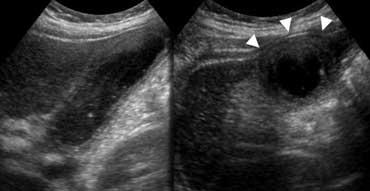

Siêu âm mặt cắt dọc và ngang cho thấy thành túi mật dày. Túi mật không ép xẹp được (‘căng phồng – hydropic’) và tạo ra dấu ấn lên thành bụng trước (đầu mũi tên).

Hình ảnh điển hình của viêm túi mật bao gồm túi mật to, căng phồng (hydropic – nghĩa là không ép xẹp được) với thành dày tại vùng đau tối đa (gọi là ‘dấu hiệu Murphy‘)

Viêm túi mật trên CT. Túi mật to với thành dày phù nề (đầu mũi tên), và có thể thấy một số dấu hiệu mờ mỡ vùng lân cận.

Túi mật viêm thường chứa sỏi hoặc bùn mật, trong khi sỏi gây tắc nghẽn có thể hoặc không thể được xác định do nằm sâu trong cổ túi mật hoặc ống túi mật.

Túi mật có thể được bao quanh bởi lớp mỡ viêm, nhưng trên siêu âm dấu hiệu này thường không thấy rõ, trong khi CT đôi khi có thể phát hiện dấu hiệu mờ mỡ.